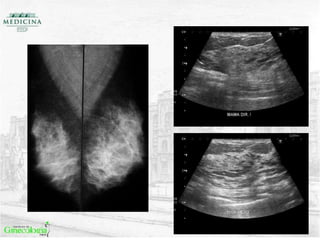

US SEGUNDO LOOK

• RESULTADO BIÓPSIA: carcinoma ductal invasor grau III;

• RESULTADO IMUNO: RE (-) / RP(-) / HER2 (-);